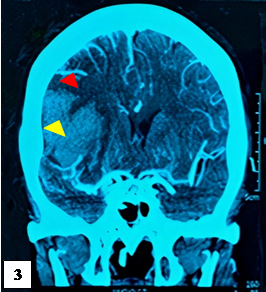

A las 3h, la escala NIHSS fue de 19 puntos, asociada a hemiplejía izquierda, lateralización de la mirada a la derecha y compromiso severo de conciencia. Se indicó una TEM cerebral sin contraste control, encontrándose foco isquémico en región parietal derecha, asociado a hemorragia subaracnoidea (figura 2). Luego de permanecer 7 horas en emergencia, ingresa a UCI. A las 12 horas se registra PA de 181/85 mmHg, asociado a taquicardia, taquipnea y febrícula (37,6°C). A las 24h se realiza una TEM cerebral y una angio-TEM que reveló un ECV isquémico con transformación hemorrágica post trombólisis, sin presencia de aneurisma roto (figura 3). La paciente permaneció en UCI en ventilación mecánica. A los 10 días, se realizó una TEM control que reveló menor volumen de hematoma en comparación al estudio tomográfico previo (figura 4). A los 20 días tras su ingreso a UCI fue dada de alta.

Área hipodensa (cabeza flecha roja) de bordes definidos asociado a disminución de la vascularización, con hematoma intraparenquimal derecho (cabeza flecha amarilla).